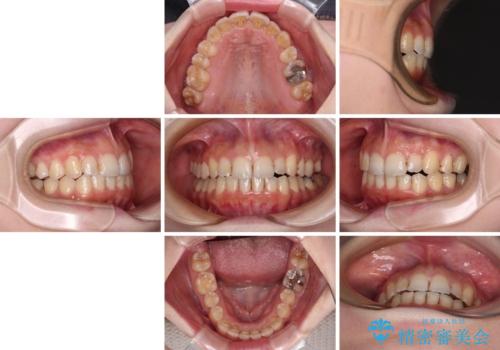

補助装置だけでなく、部分的にワイヤー矯正も使用しましたが、上下のスペースは改善しきれず、側切歯(前から2番目の歯)や顕著な八重歯は、インビザラインで治療するには限界があることがよく分かりました。

より良い仕上がりを希望される場合には、ワイヤー装置による矯正治療がお勧めとなります。